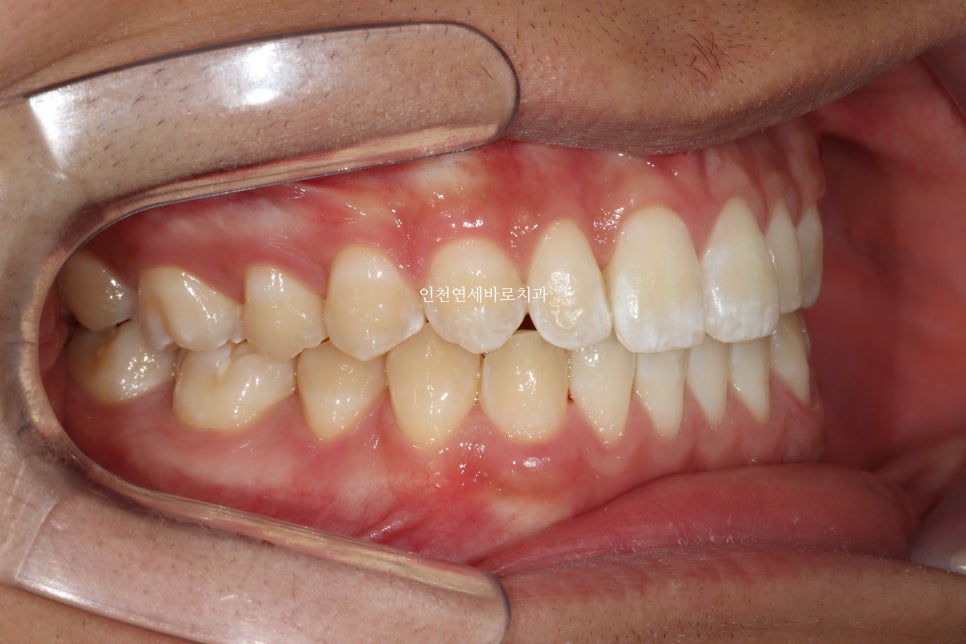

치료 받으러 온 고1 남학생입니다.

앞니가 벌어진 것도 문제였지만

화살표쪽에 보이는 반대교합도 문제였습니다.

문제가 되었던 오른쪽 어금니 교합도 좋게 마무리 하였습니다.